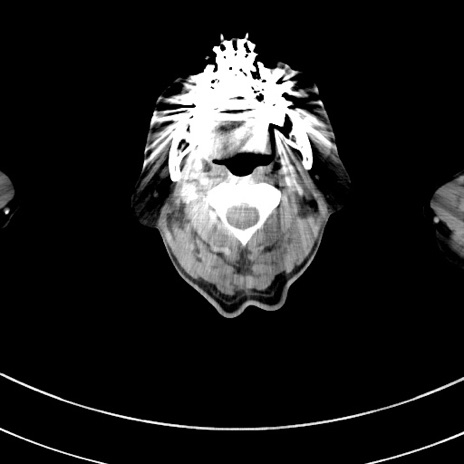

冠状断像

【症例】 60歳代男性

【主訴】 黒色吐物

【現病歴】 4日前から嘔気自覚、2日前の朝食後にも嘔気あり、自分で手で嘔吐反射起こし嘔吐したところ血が混ざっていたため受診。

【既往歴】 5年前汎発性腹膜炎を伴う急性虫垂炎で手術、高血圧、前立腺肥大症、高脂血症

【身体所見】 腹部正中に手術癩痕あり 腹部平坦・軟圧痛なし膨満感あり

【データ】WBC 8400、CRP 4.54